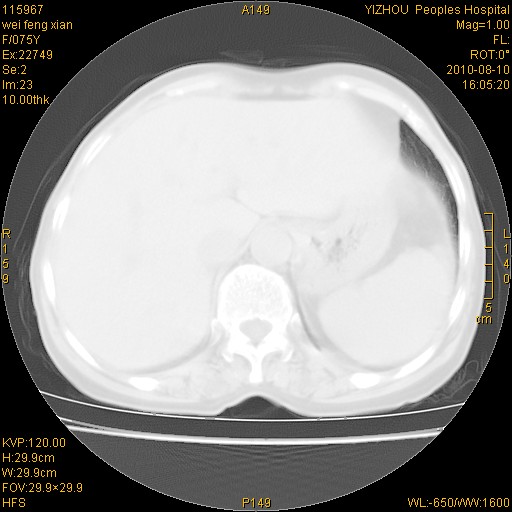

标题: CT28313:两肺弥漫性病变 [打印本页]

标题: CT28313:两肺弥漫性病变

女,75岁,患者反复头昏乏力面色苍白3年,再发10天入院。临床贫血查因。

双肺间质增生并右肺上叶炎性改变,不除外右肺上叶结核病肺内播散

考虑慢支伴右上肺慢性感染可能性大,建议结合临床排外尘肺可能。

考虑尘肺可能性大.

考虑右肺上叶炎症合并双肺结核可能性大,建议上传纵隔窗ct图片。

双肺结核可能性大

考虑尘肺并结核;右上肺支气管扩张!

结核、尘肺、支气管肺泡癌都不能除外

右肺上叶继发性肺结核伴肺内血型播散!

考虑右肺上叶继发性肺结核伴两肺播散。